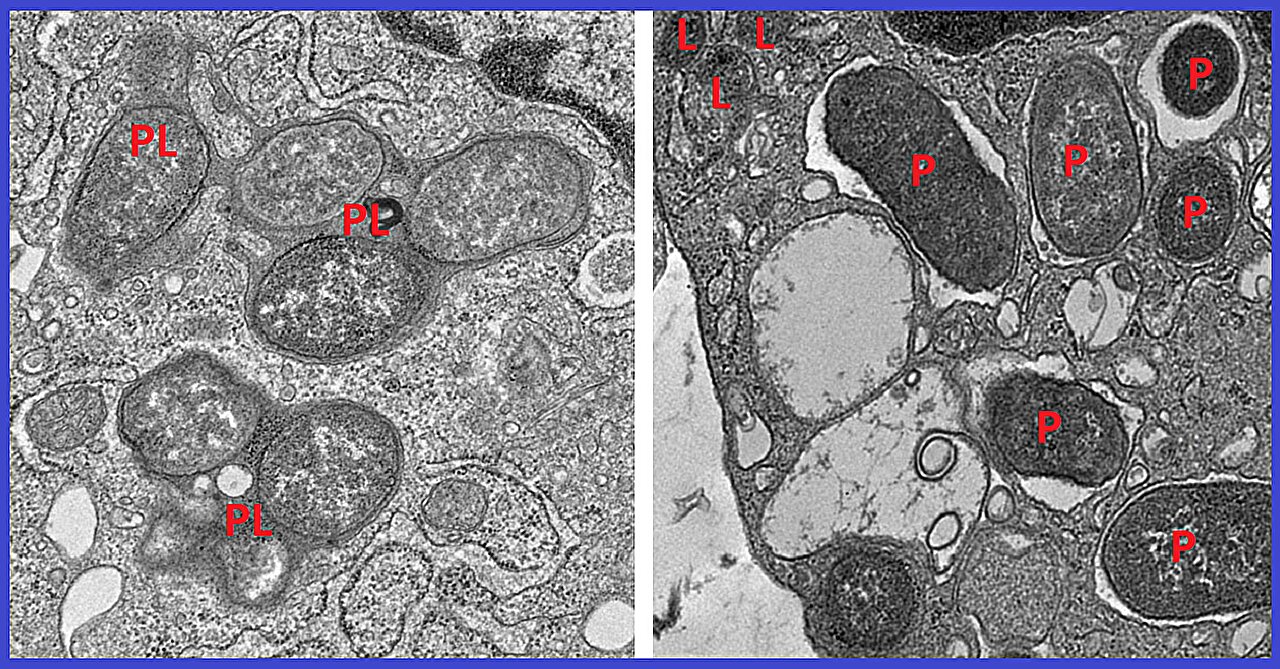

- When this partnership is disrupted, it leads to a dangerous imbalance between inflammatory and non-inflammatory macrophages.